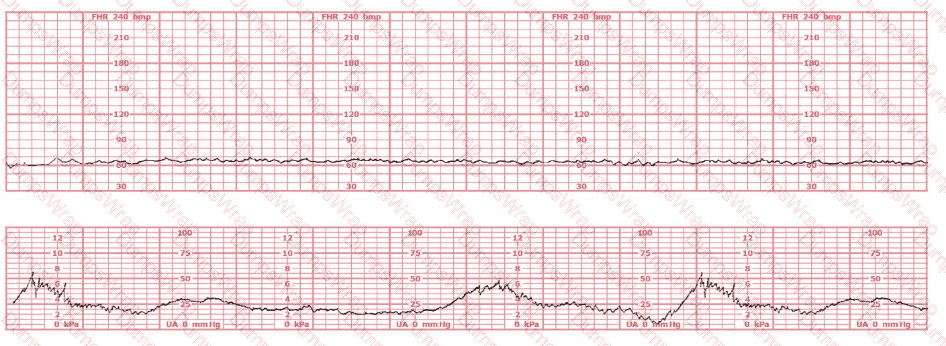

The fetal heart rate tracing shown is obtained upon the woman's admission to labor and delivery. This tracing is most consistent with what maternal condition?

Options:

Eisenmenger's syndrome

Sickle cell anemia

Systemic lupus erythematosus

Answer:

BExplanation:

Comprehensive and Detailed Explanation From Exact Extract (NCC C-EFM sources: AWHONN, Miller’s Pocket Guide, Menihan, Simpson, Creasy & Resnik, 2025 Candidate Guide)

The tracing displays baseline fetal bradycardia, with a rate near 100 bpm, minimal variability, and preserved periodic response. According to AWHONN’s Fetal Heart Monitoring Principles & Practices and Menihan’s Electronic Fetal Monitoring, maternal conditions that reduce oxygen-carrying capacity—including maternal anemia—can lead to lower fetal oxygen delivery, prompting a fetal compensatory bradycardic baseline.

Creasy & Resnik’s Maternal-Fetal Medicine notes that sickle cell anemia decreases maternal hemoglobin function even when maternal vital signs appear stable, reducing uteroplacental oxygen transport. Fetuses of mothers with sickling disorders may demonstrate lower resting fetal heart rates due to chronic mild hypoxemia.

Conversely, Eisenmenger’s syndrome is associated with severe maternal cyanosis and high fetal mortality, often producing late decelerations and growth restriction rather than mild bradycardia. Systemic lupus erythematosus (SLE) is commonly associated with heart block (especially with anti-Ro/SSA antibodies), which is not displayed here, as true heart block presents with a fixed atrial–ventricular dissociation and FHR < 60 bpm.

Thus, based on fetal physiology and maternal disease correlations taught in NCC-recommended sources, the tracing is most consistent with maternal sickle cell anemia.